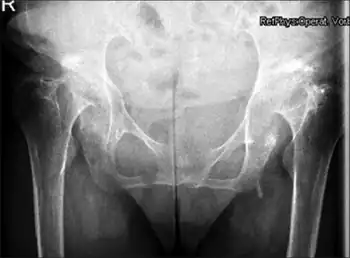

| Radiographic criteria for protrusio acetabuli are an abnormally positioned acetabular line, a center-edge angle of Wiberg of >40°, and the crossing of teardrop by ilio-ischial line | |

Protrusio acetabuli is an uncommon defect of the acetabulum, the socket that receives the femoral head to make the hip joint. The hip bone of the pelvic bone/girdle is composed of three bones, the ilium, the ischium and the pubis. In protrusio deformity, there is medial displacement of the femoral head in that the medial aspect of the femoral cortex is medial to the ilioischial line. The socket is too deep and may protrude into the pelvis.[1]